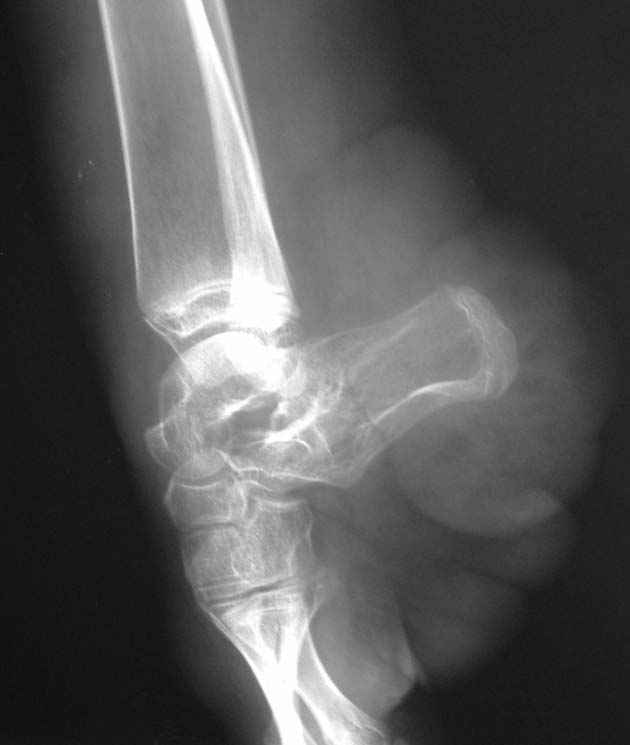

От I беременности, протекавшей с анемией, ОРВИ, угрозой прерывания, I преждевременных патологических родов, девочка 1100 гр., дл. 36 см, Апгар 3/5 б. Отмечается гипоксическое поражение ЦНС, с-м возбудимости, гемангиоматоз, недоношенность III ст. Инвалид детства, на Д-учете.Диагноз: Синдром Клиппеля-Тренона-Вебера, врожденная аномалия левой нижней конечности, деформация левой стопы, ЗТРР в легкой степени, дислалия, лимфоаденоматоз. В 2000 г. - нейро-атритический диатез, ацетонемическое состояние, задержка развития пренатального детерминирования, гипотрофия III ст.Цитогенетическое обследование 09.2008.Объект исследовани: культура лимфоцитов периферической крови, метафазные пластинки хромосом, G-окрашивание.Кариотип 46,ХХЗаключение: хромосомной патологии не выявлено.Носит ортопедическую обувь.Левая нижняя конечность - выраженное ангиоматозное поражение, гигантизм, опережает здоровую конечность на 8 см в длину, постоянный ускоренный рост, контрактуры крупных суставов, стойкая эквинусная установка стопы, не опорна.Рассматривались предложения:1. Ампутация с дальнейшим протезированием.2. Удлинение здоровой конечности.3. Хирургическое устранение эквинуса с последующим удлинением здоровой конечности.Ваше мнение, идеи, комментарии? Выполнение 3 варианта в условиях ангиоматозного поражения? Иные методы, подходы?Заранее благодарю!

По представленным фото и рентгенограммам диагноз: Синдром Клиппеля-Треноне-Вебера (КТВ) вызывет сомнения. Для синдрома КТВ очень характерно наличие варикозно расширеных вен, каппилярных гемангиом на туловище и конечностях, гигантизм конечности при отстуствии грубых деформаций суставов, характерный "крупнозернистый" вид кости на рентгенограммах, отстутвие призанков поражения ЦНС и эндокринных нарушений. Соответвенно и ортопедический этап у этих больных проще: достаточно удлиннить здоровую конечность (фото в приложении).

Имея опыт ортопедического лечения больных с синдромом КТВ, я не имею опыта лечения больных, с такими аномалиями, которые представлены Вами. Чисто теоретически, могу предположить, что лечение надо разбить на несколько этапов: 1 - совместно с пластическими хирургами удалить опухолеподобные массы на стопе, сделав ее приглдной к одеванию обуви, выполнить закрытую корекцию деформации стопы и метатарзальный, а возможно,и большеберцовый эпифизеодез. Меняя выстоту ортопедической обуви на здоровой ноге по мере ее роста обеспечить больной максимальную опороспособность больной ноги. По окончанию периода второго ростового спурта при удовлетворительной опороспособности больной ноги выполнить 2 этап - выполнить эквализацию конечностей (удлиннить здоровую?).

При неудовлетворительных резкльтатах первого этапа - возможно думать и об ампутации. Из послеоперацинных осложнений данной патологии при любом типе операции (даже ампутациях)R.M. Letts (1977) отмечал: профузное кровотчение в раннем п/о периоде, выраженный и длительно сохрянющийся отек, замедленное заживление ран.